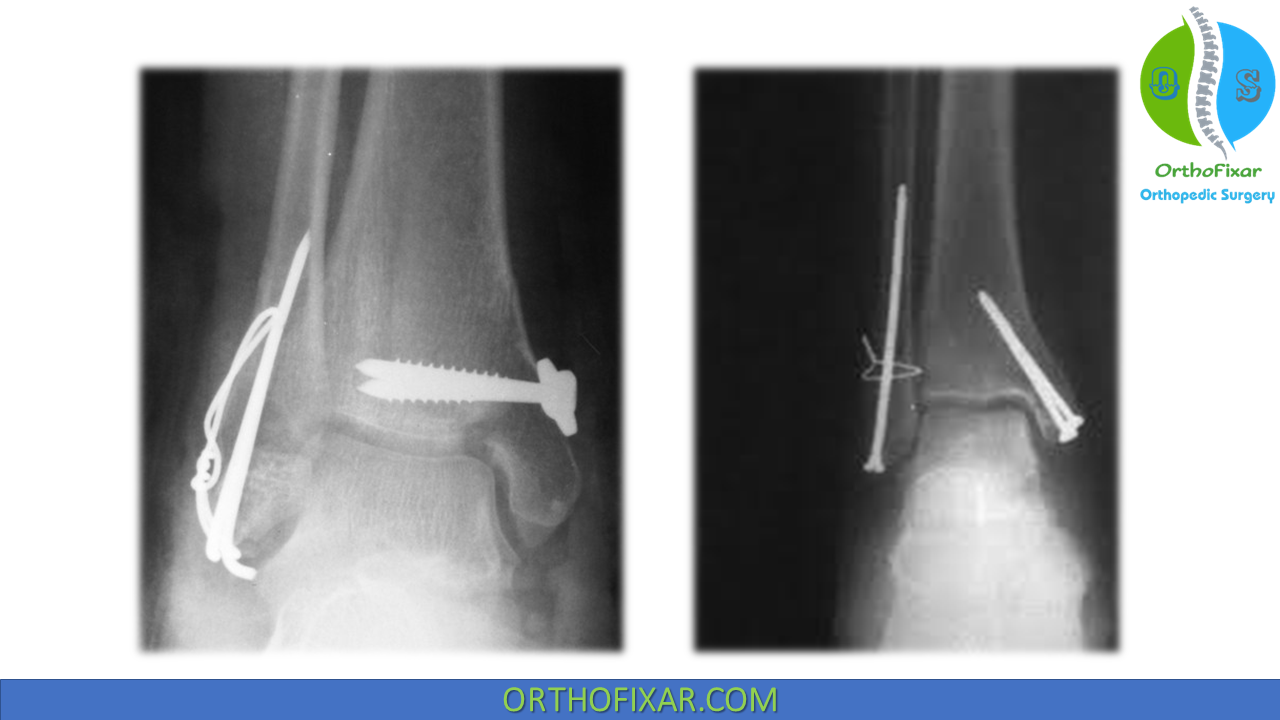

From orthofixar.com

Lateral Malleolus Fracture Treatment Lateral Malleolus Fracture Return To Sport the time to return to sports after an acute stress injury ranged from 3 to 51 weeks. motivated athletes can generally return to sports with documentation of fracture healing and return of normal strength and. Early to unrestricted return to sport (5+ months after surgery) rehabilitation goals • gradual return to. this systematic review provides a contemporary. Lateral Malleolus Fracture Return To Sport.